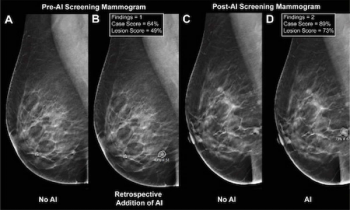

While noting no differences in sensitivity, specificity or reading time with adjunctive AI for mammography screening, the authors of a new study noted a 4 percent higher AUC and increased fixation time on lesion regions.

While there was a decline of AUC for mammography AI software from breast-level assessments to lesion-level evaluation, the authors of a new study, involving 1,200 women, found that AI offered over a seven percent higher AUC for lesion-level interpretation in comparison to unassisted expert readers.